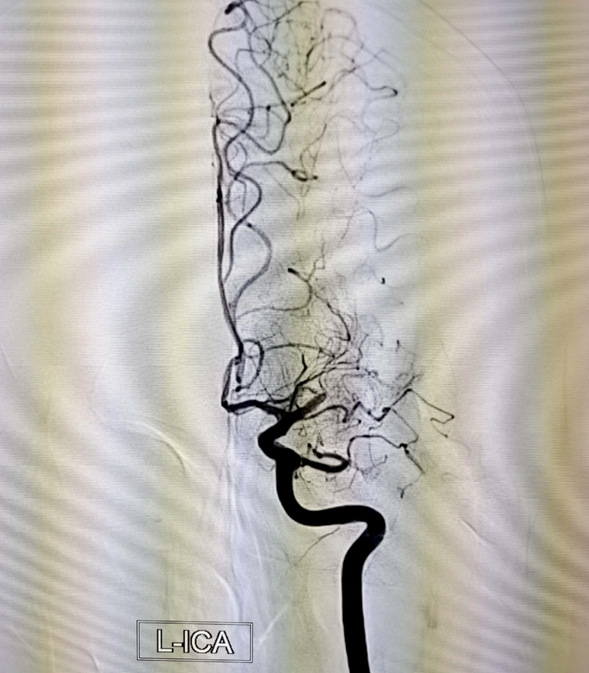

介入科主任刘琳与副主任莫庆国与患者家属交代病情,患者家属同意急诊取栓治疗,经商议后决定行BADDASS治疗,三件套组合:BGC+中间导管+长取栓支架,交换8F动脉鞘,引入BGC:8F×95cm;颅内支持导管:5F*125cm;取栓支架:4mm*30mm至远端病变血管,透视下释放取栓支架至病变血栓处,停留8分钟后取出大量血栓,取栓成功。复查造影见左侧经内动脉、左侧大脑前动脉、左侧大脑中动脉显影正常,血流改善,各分支显影良好,M1段未见明显狭窄,术中复查C臂CT未见颅内出血。术后患者意识清楚,问话对答切题。